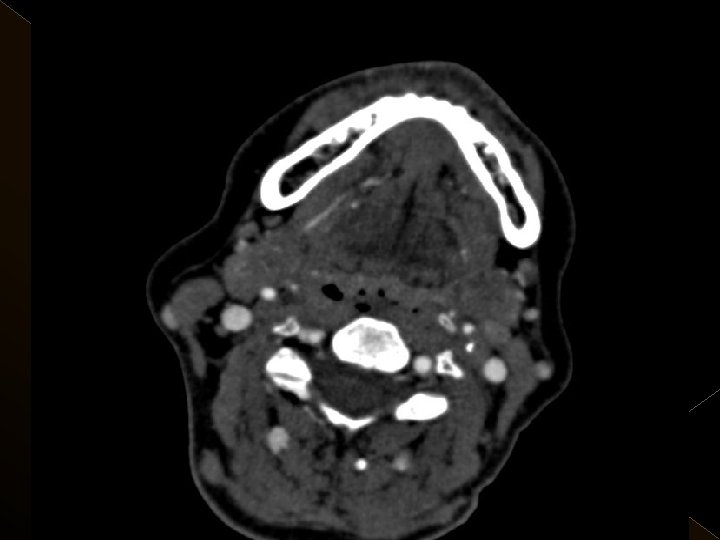

Görüntüleme İşlem öncesi § Bazal kontrastsız BT § BT anjiografi (varsa perfüzyon BT ) § MR (DW, ADC) İşlem sonrası § MR ( DW, ADC, SWI) § 24. saatte kontrol BT veya MR

� 25 hasta (16 K, 9 E) , 27 vaskuler okluzyon � 16 orta serebral arter (MCA), � 6 baziler arter ve � 5 internal karotis arter (İCA) düzeyinde olmak üzere � Toplam 25 hasta, 27 tıkanıklığa (6 sı hariç) iv tpa sonrası endovaskuler yolla müdahale edildi

KOMPLİKASYONLAR Ponksiyon bölgesi komplikasyonları � Trombektomi stentine ait komplikasyon (*1) � Diseksiyon(*2) � Karotikokavernöz fistül (‘ 1) � Hemorajik komplikasyonlar(‘ 5) Semptomatik-nonsemptomatik � İskemik komplikasyonlar (3) � Reoklüzyon (2 i. a) � Kontrast madde nefropatisi �